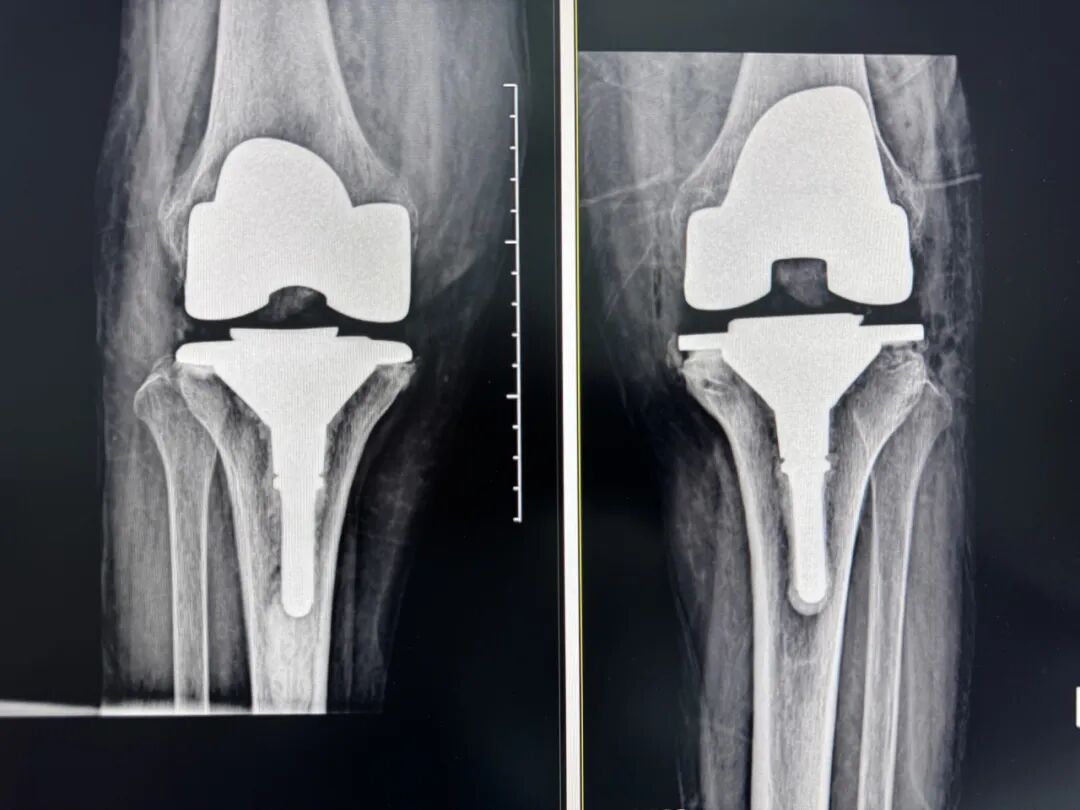

"阿婆,您慢慢來,扶著我就行!"在醫(yī)護(hù)人員攙扶下,85歲的沈家門居民鄭阿婆(化名)術(shù)后第一天便穩(wěn)穩(wěn)邁出重生后的第一步。三天前因雙膝重度骨性關(guān)節(jié)炎被輪椅推進(jìn)醫(yī)院的她,如今已能獨(dú)立行走、自如生活,激動(dòng)地感嘆"真像換了雙新腿"。這場(chǎng)醫(yī)學(xué)奇跡的背后,是廣安醫(yī)院羅軍院長(zhǎng)的醫(yī)療團(tuán)隊(duì)運(yùn)用AI三維規(guī)劃人工膝關(guān)節(jié)置換術(shù)創(chuàng)造的。

術(shù)前:AI通過CT掃描生成毫米級(jí)膝關(guān)節(jié)三維模型,為假體安裝設(shè)計(jì)出誤差小于1毫米的精準(zhǔn)方案 術(shù)中:智能導(dǎo)航系統(tǒng)如同"透視眼",引導(dǎo)醫(yī)生避開密集的神經(jīng)血管網(wǎng),截骨更精準(zhǔn),出血僅100ml 術(shù)后:當(dāng)天鄭阿婆即開始抬腿的康復(fù)訓(xùn)練,24小時(shí)內(nèi)扶助行器下地行走,三天后已能在病房走廊獨(dú)立行走,完成洗漱用餐 兩周后健步出院時(shí),女兒含淚感慨“之前擔(dān)心她年紀(jì)大扛不住手術(shù),沒想到恢復(fù)這么快!現(xiàn)在每天散步比我還精神。知道技術(shù)這么先進(jìn),真該早點(diǎn)來!”

"這就像給傳統(tǒng)手術(shù)裝上了自動(dòng)駕駛系統(tǒng)。"主刀醫(yī)生羅軍副院長(zhǎng)用生動(dòng)比喻解析技術(shù)突破。AI不僅實(shí)現(xiàn)假體“量身定制”,使用壽命可達(dá)20年以上,更通過三維路徑規(guī)劃將康復(fù)周期壓縮,實(shí)現(xiàn)術(shù)后24小時(shí)下地,2周回歸正常生活。同時(shí),AI會(huì)避開重要組織,具有出血少、感染風(fēng)險(xiǎn)低的特點(diǎn)。專家特別提醒,當(dāng)出現(xiàn)夜間持續(xù)性關(guān)節(jié)疼痛、步行能力低于10分鐘或關(guān)節(jié)畸形時(shí),應(yīng)及時(shí)就醫(yī)評(píng)估,"別等到關(guān)節(jié)'報(bào)廢'才手術(shù)"。